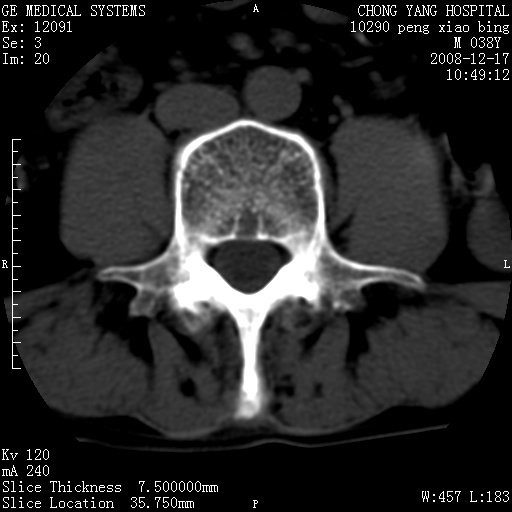

探讨强直性脊柱炎的CT、X线平片表现,及其诊断价值.材料和方法:回顾性分析53例强直性脊柱炎的CT、X线平片征象并根据纽约标准分期.结果:53例中,0期正常0例;Ⅰ期可疑改变CT 7例,X线平片2例;Ⅱ期轻度异常CT 9例,X线平片6例;Ⅲ期明显异常24例;Ⅳ期关节骨性强直13例(Ⅲ,Ⅳ期CT,X线平片检出率相同).结论:CT检查能对强直性脊柱炎做出正确分期,对临床诊断及治疗预后有较高的准确性,优于X线平片。